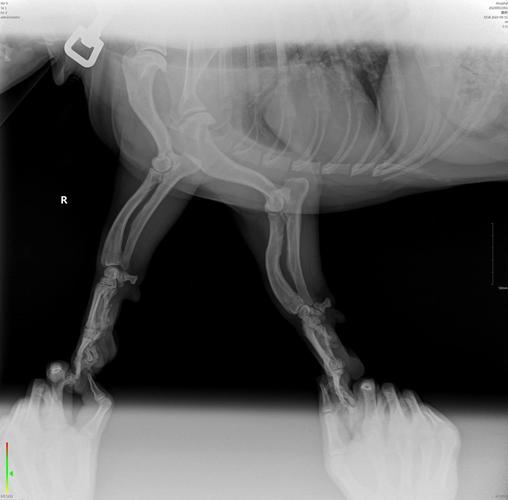

狗狗腿瘸了,想给它拍个片子看看有没有问题,想问一下拍个片子大概费用是...

正规的宠物医院都可拍片,拍片的费用在60至80元。

这个比较复杂。首先是确定腿瘸的原因,从描述来看,应当在1000元以里可以解决。

狗狗拍一个x光片多少钱一般宠物医院的标价在80『1』20元/体位/张,比如胸部,腹部,腿部这样区分,通常为了确诊,同样的部位会拍两个体位,也就是160『2』40元。人去的当然不能让狗进啦,避免交叉感染嘛。正规的宠物都可拍片,拍片的费用在60至80元。那么狗狗做B超一般多少钱。

为了避免交叉感染,人去的医院通常不允许狗狗进入。正规宠物医院拍片的费用大约在60至80元。 狗狗做B超的费用通常比拍片便宜,一般在几十元人民币。不同宠物医院的收费标准可能有所不同。 狗狗腿部拍片的费用根据宠物医院或宠物店的不同而有所变化,费用在80元到150元不等。